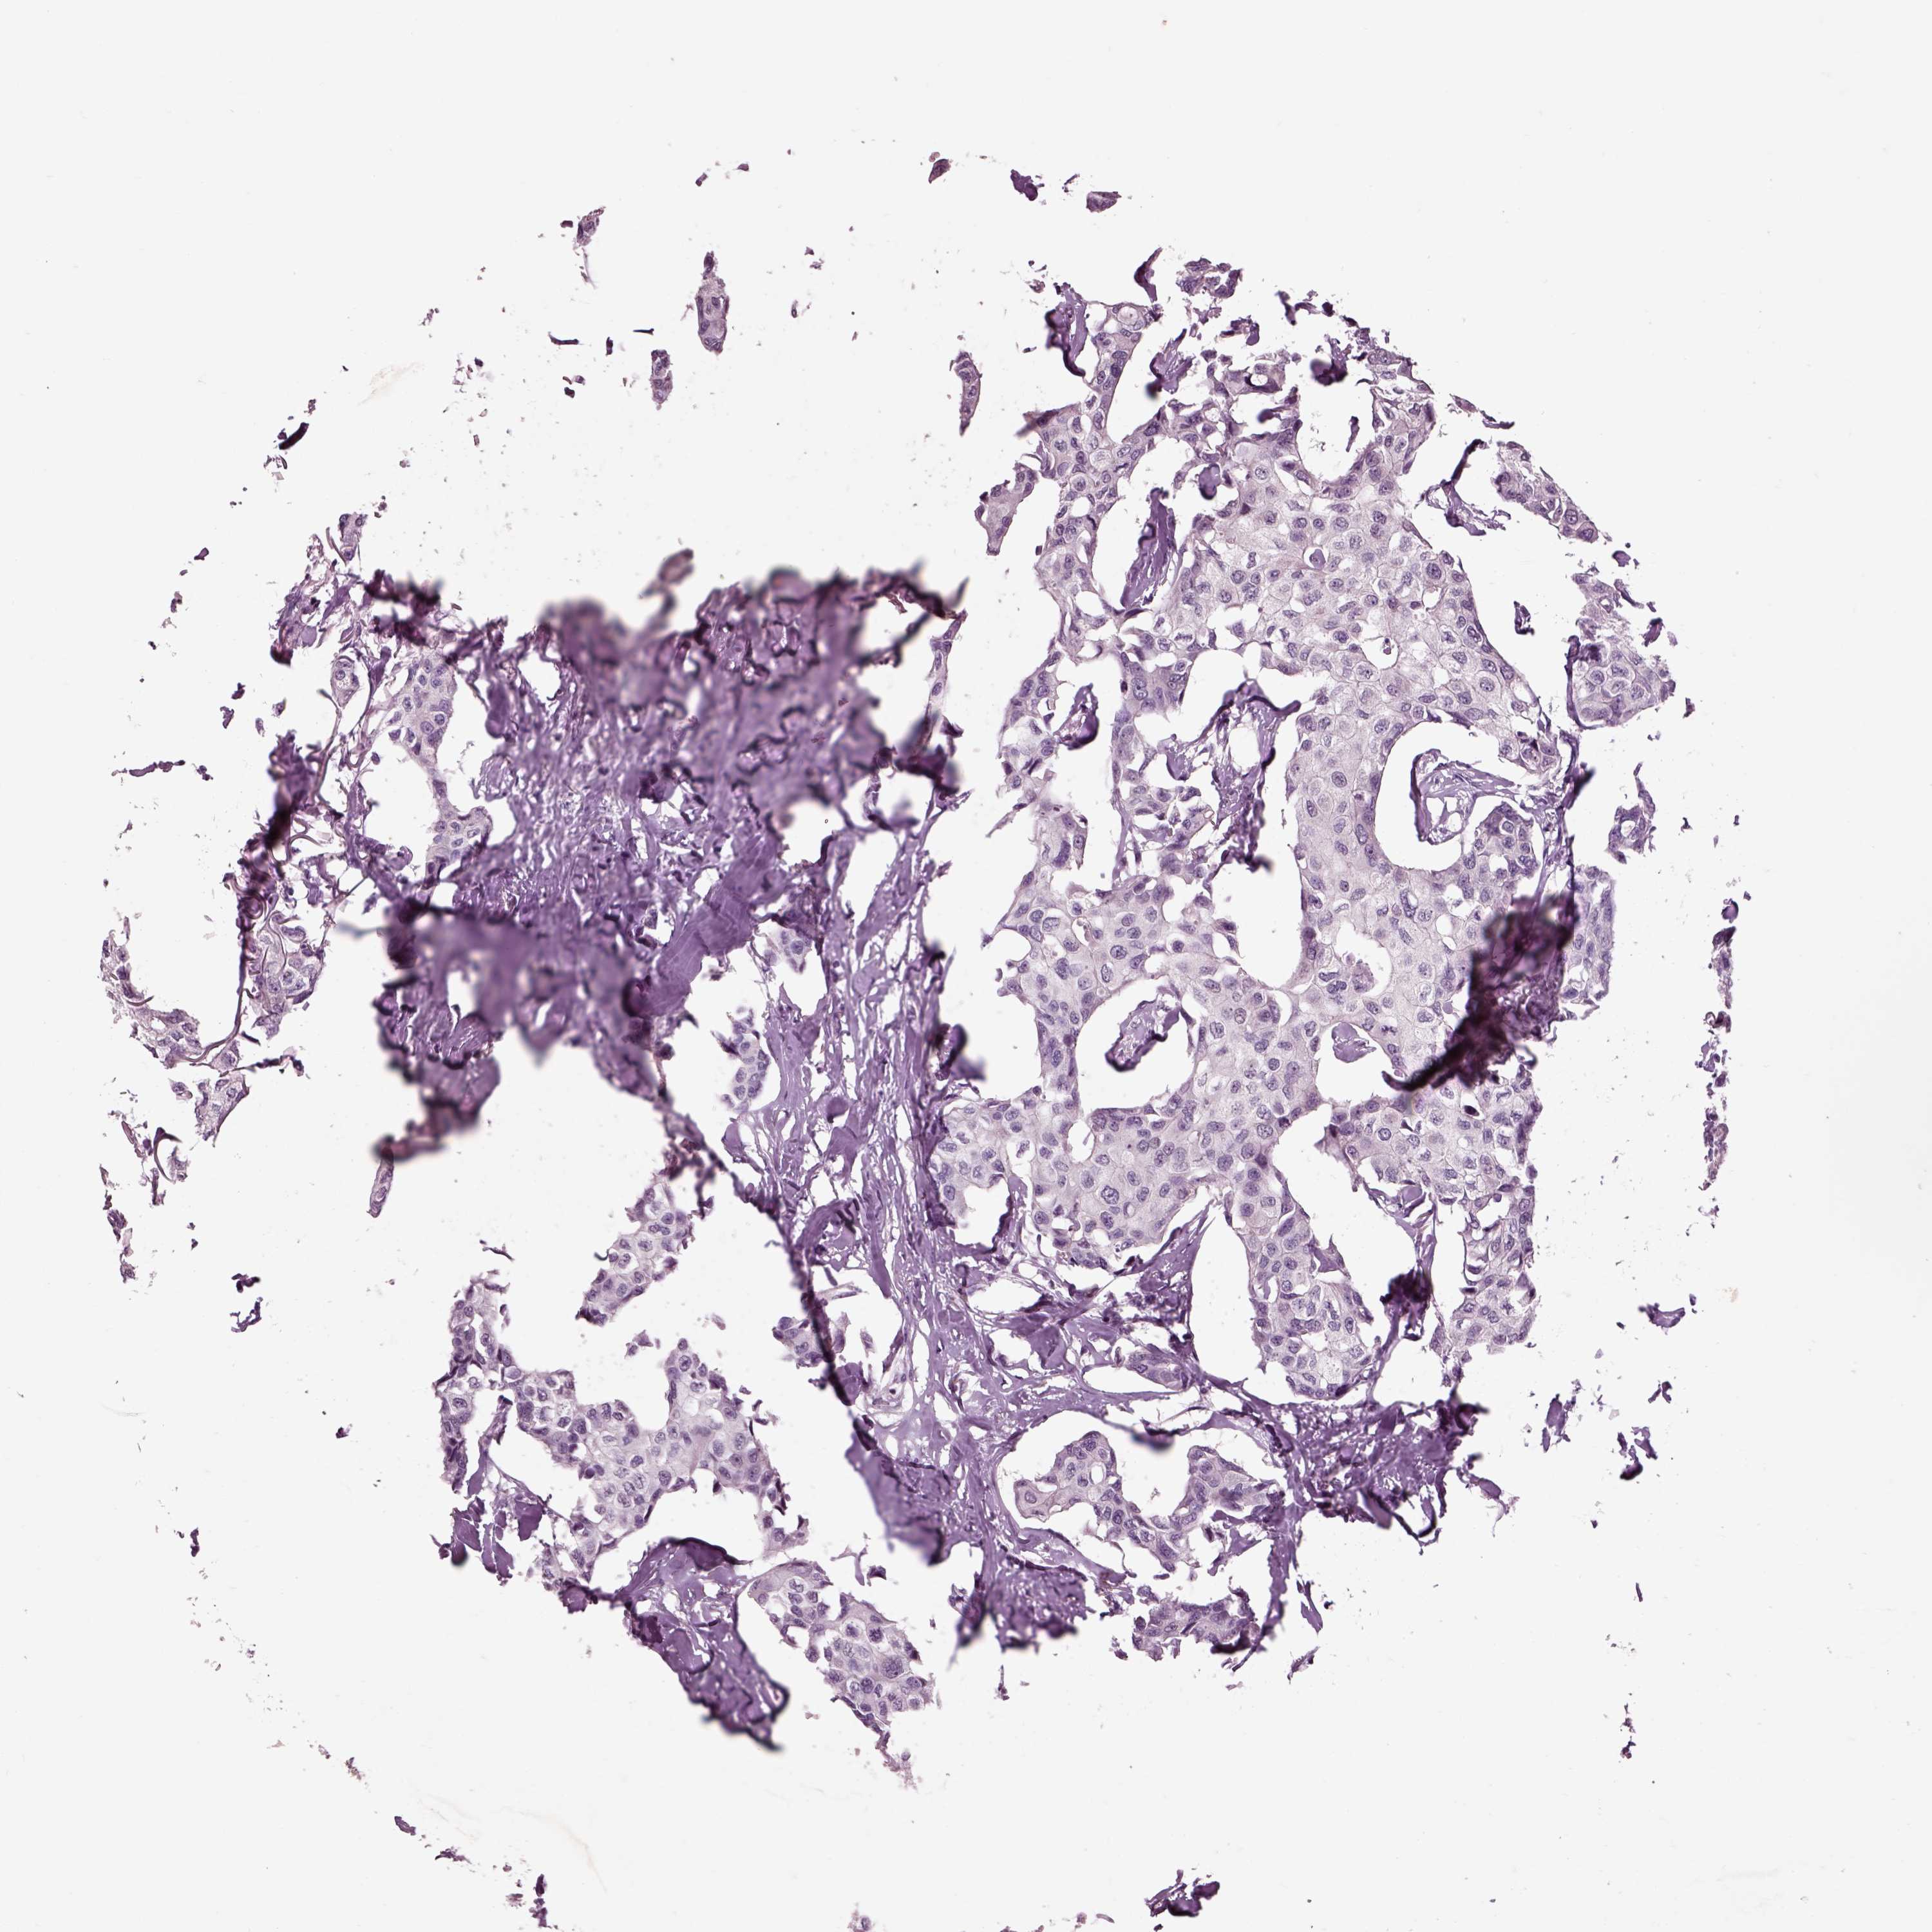

Breast cancer

Human cancer